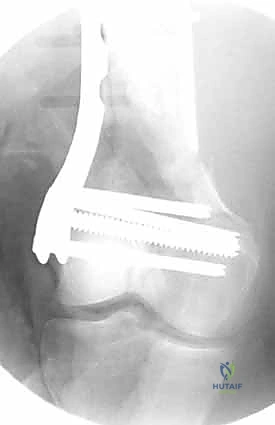

المرحلة الرابعة: التثبيت النهائي بالشرائح والمسامير (Fixation)

يتم استخدام "شرائح الإغلاق التشريحية" (Anatomical Locking Plates) المصنوعة من التيتانيوم عالي الجودة. هذه الشرائح مصممة خصيصاً لتأخذ شكل الجزء السفلي من عظم الفخذ. يتم تمرير الشريحة أسفل العضلات وتثبيتها بمسامير تغلق داخل الشريحة نفسها (Locking Screws)، مما يوفر ثباتاً ميكانيكياً هائلاً، حتى في حالات العظام الهشة.

في بعض الحالات المعقدة جداً، قد يتطلب الأمر استخدام شريحتين (Dual Plating) لضمان عدم تحرك الكسر أثناء فترة التعافي.